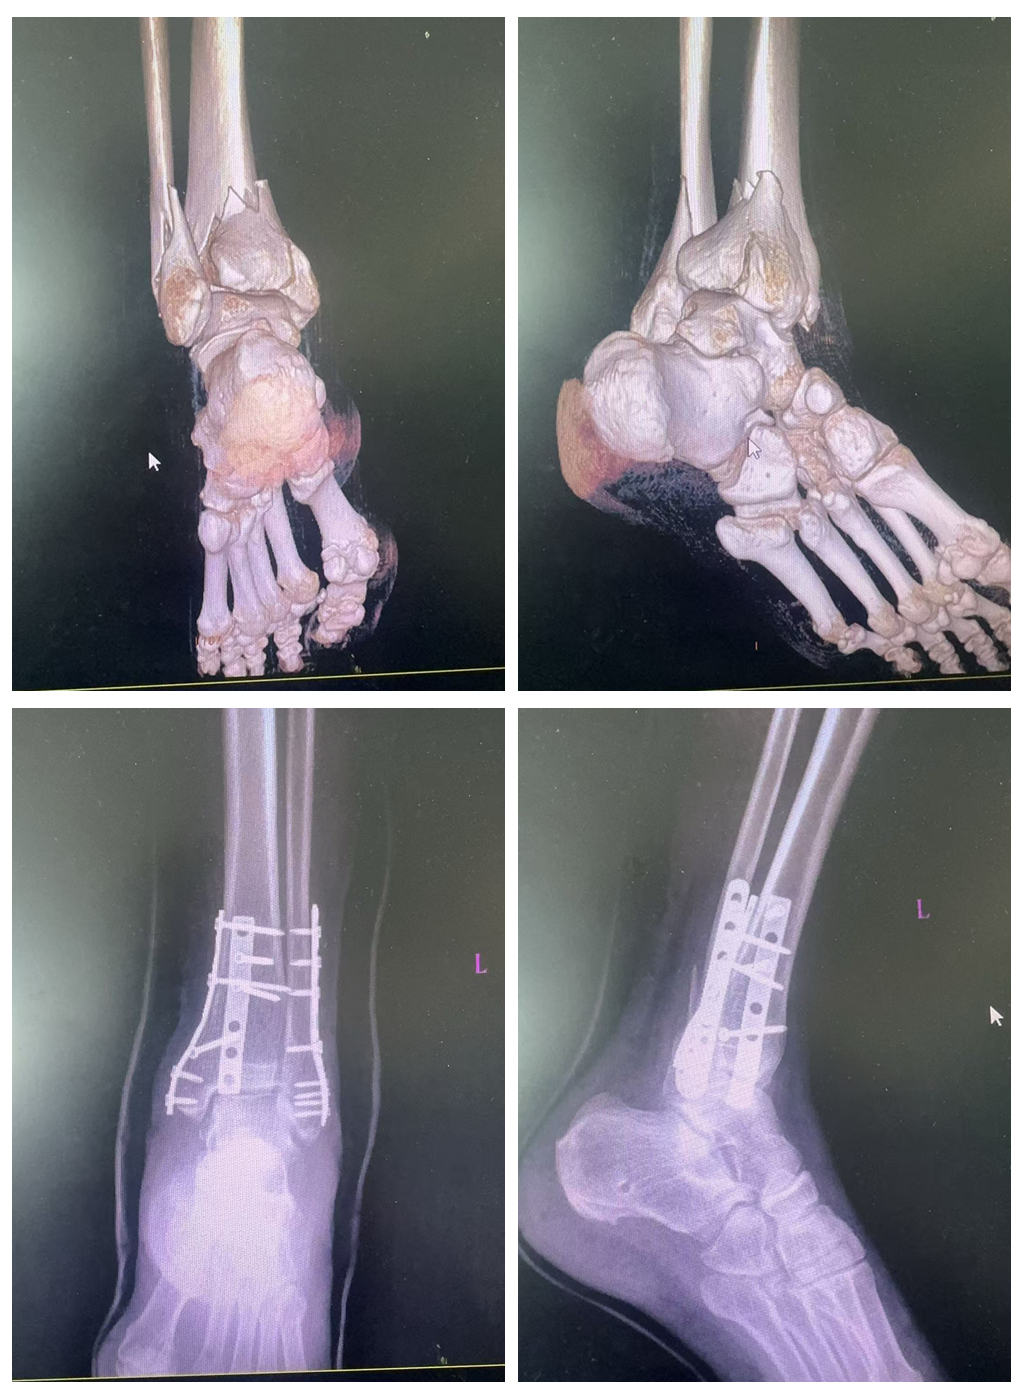

李先生因意外摔伤导致左踝部严重损伤,X光检查显示其左外踝、后踝骨折伴明显移位,踝关节半脱位。面对如此严重的损伤,患者及家属最初考虑转往合肥治疗。霍邱县人民医院骨科副主任医师王敬瓦接诊后,立即联系安徽医科大学第二附属医院朱楠主任进行会诊。作为省级区域(专科)医疗中心驻点专家,朱楠主任迅速参与制定治疗方案,并现场指导手术。

医疗团队为患者施行了踝关节骨折脱位切开复位钢板内固定术,术中采用微创改良技术,仅通过2-3厘米小切口完成操作。该技术具有组织损伤小、感染风险低、出血少、手术时间短等优势,特别适合老年患者。在朱楠主任的指导下,手术团队精准完成骨折复位和钢板固定,为患者术后康复奠定了良好基础。

经过系统治疗和康复训练,患者踝部肿胀疼痛完全消失,骨折愈合良好,现已恢复正常行走功能。患者家属表示:"不用奔波至合肥,在家门口就享受到省级专家的技术服务,既节省了费用又方便了就医,对此我们深表感激。"